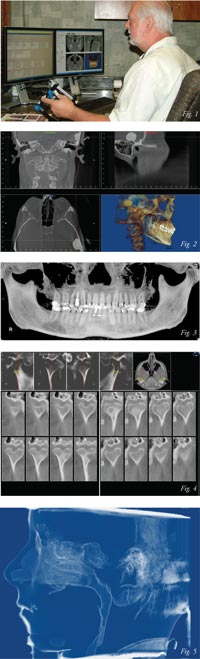

Roncone: I have been fortunate to have a very experienced

medical radiology technician to run our CBCT. She studies each

scan and will alert me to any potential problem areas she detects. I then will spend about 20-25 minutes on the entire scan. We

have a “basic” number of areas for each patient that I will always

check ie, various views of the TMJ, airway, panoramic view,

frontal and lateral cephalograms and any areas of particular

interest to me based on the clinical examination. I then will look

at the 3D view from various angles, scan up and down the airway,

check areas of bone around suspect teeth, etc. I use all

records simultaneously while going through a drastic checklist so

that hopefully nothing is missed. (See Figure 1)

Roncone: The diagnostic benefits of using the cone beam

have been dramatic. What is amazing to me is what I was not

seeing in typical orthodontic diagnostic records. The clarity of

the TMJ; airway from five different views; anomalies and

pathology would never have been previously detected.

Additionally, the various filters available make the tracing of

the cephs much easier and more accurate than in the past. (See

Figures 2-5).